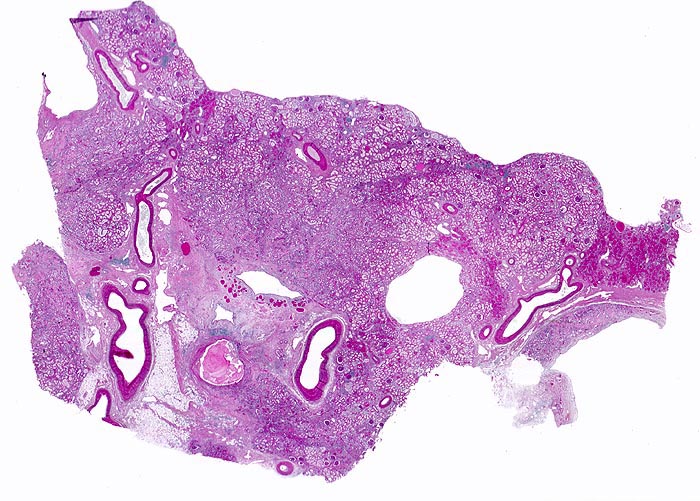

PathoPic – image database / PathoPic ID 5011 - chronische Pyelonephritis

chronische Pyelonephritis

Die Nierenoberfläche ist grobhöckrig deformiert aufgrund muldenförmiger narbiger Einziehungen und zwischen den Narbenbezirken vorgewölbten erhaltenen Parenchymabschnitten. Infolge reaktiver Gefässwandverdickung erscheinen die Gefässe auffallend prominent. Im angeschnitten Nierenbecken: "scholliges Harnmukoid".

Makroskopisch ist die Nierenoberfläche grobhöckrig deformiert durch zahlreiche Narben mit teils rotem, teils weissem Grund. Beide Nieren sind verkleinert (Gewicht beider Nieren zusammen 180g). Das leicht ausgeweitete und gerötete Nierenbecken enthält mehrere kleine harte zackig begrenzte grauschwarze Kalziumoxalatsteine.

Nephrolithiasis und wiederholte akute pyelonephritische Schübe beidseits. Arterielle Hypertonie.

Histologie

Scan